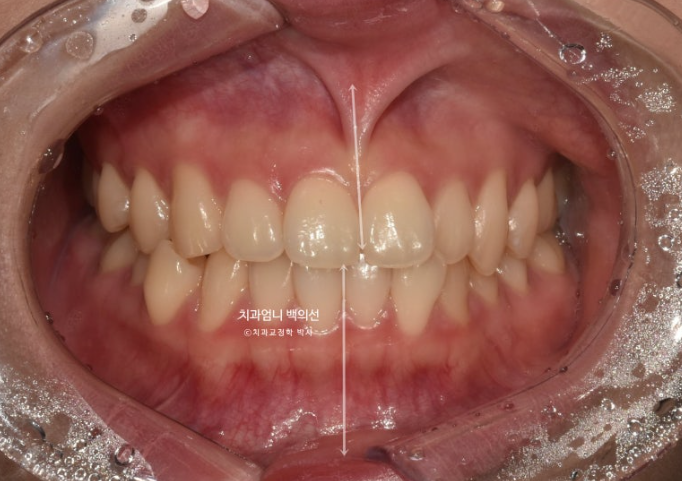

23년 7월 교정치료를 위해 내원한 환자분입니다.

고치고 싶은 것은 중심선 비대칭과 덧니입니다.

왼쪽 위 작은어금니 하나가 선천적으로 없으면 이로 인해 그쪽으로 윗니 중심선이 돌아가 있습니다.

중심선이 처음에 비해 좋아졌으나 아직 불일치가 보입니다.

고무줄 처방으로 인해 중심선은 정확하게 맞으며

교합은 나쁘지 않습니다.

배열도 좋습니다.

웃는 사진에서는 결손치 쪽으로 돌아가 있던 윗니 중심선이 드디어 코와 인중을 만나게 되었습니다.

그러나 왼쪽 앞니 하나가 미미하게 치축이 기울어져 보입니다.